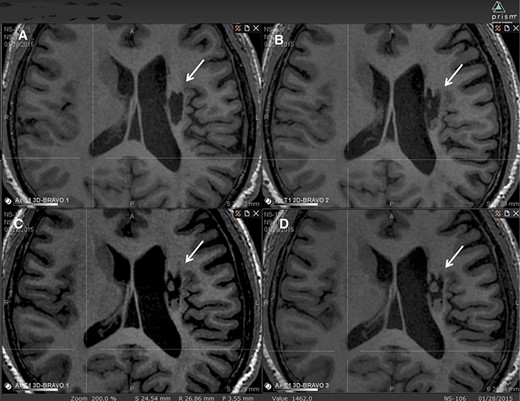

圖中顯示了B組 (#106) 受試者在T1MRI上隨時(shí)間的變化。

(A):基線時(shí),(B) 6個(gè)月隨訪時(shí),(C) 12個(gè)月隨訪時(shí),(D) 24個(gè)月隨訪時(shí)。箭頭表示梗塞腔。

可以看到兩個(gè)組織團(tuán)塊,在基線時(shí)不存在,推測(cè)是來(lái)自植入的NSI-566,隨著時(shí)間的推移,它們似乎慢慢填滿了腔體。